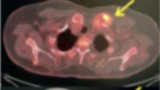

Malignancy or Not? Role of 18F-FDG PET/CT in Solving the Diagnostic Dilemma in Multiple Myeloma Misdiagnosed as Rheumatoid Arthritis: Pictorial Series